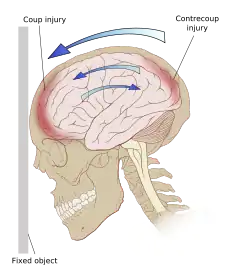

حتى في حالة عدم وجود تأثير، تسارع أو تباطؤ الرأس يمكن أن يسبب الإصابة. ومع ذلك في معظم الحالات يكون السبب فيها مزيج من الصدمة والتسارع.[30] وتسمى القوى التي تنطوي على اصطدام الرأس أو ضربه بشيء ما بالقوة المتصلة أو تأثير التحميل، وهي السبب في معظم الإصابات البؤرية، بينما يطلق على حركة الدماغ داخل الجمجمة القوة غير المتصلة أو التحميل بالقصور الذاتي، وعادة ما يسبب إصابات منتشرة.[12] ويسبب الهز العنيف للرضع الذي يسبب متلازمة الرضيع المهزوز إصابات منتشرة.[60] في تأثير التحميل، ترسل القوة موجات صادمة من خلال الجمجمة والدماغ، مما يؤدي إلى تلف الأنسجة.[30] ويمكن أيضا أن تدمر الموجات الصادمة الناجمة عن إصابات الاختراق الأنسجة على طول مسار القذيفة، مما يضاعف الأضرار الناجمة عن القذيفة نفسها.[15]

قد تحدث الأضرار مباشرة تحت موقع الصدمة، أو قد تحدث على الجانب المقابل لها (إصابة الضربة ورجع الضربة على التوالي).[59] فعندما يؤثر جسم متحرك على الرأس الثابت، تكون إصابات الضربة نموذجية،[61] في حين أن إصابات رجع الضربة تنتج عادة عندما يضرب الرأس المتحرك جسم ثابت.[62]